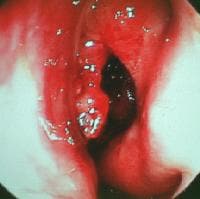

The range of physical findings on examination is typically broad, from nasal airway obstruction resulting from intranasal inflammation and polyposis, as depicted in the 1st image below, to gross facial disfigurement and orbital or ocular abnormalities. The author and colleagues reported that facial dysmorphism, consisting of proptosis, as depicted in the 2nd image below, telecanthus, and malar flattening, more often was seen in children than in adults (42% vs 10%) in their series of 151 patients, including 107 adults aged 18 years or older and 44 children aged 17 years or younger, as depicted in Table 2 below.

View just inside the nasal vestibule showing diffuView just inside the nasal vestibule showing diffused polyposis extending into the anterior nasal cavity and vestibule; the septum is on the right, and the right lateral vestibular wall (nasal ala) is on the left. The polyps all are in the center. The polyps almost hang out of the nasal vestibule.A 15-year-old boy with allergic fungal sinusitis cA 15-year-old boy with allergic fungal sinusitis causing right proptosis, telecanthus, and malar flattening; the position of his eyes is asymmetrical, and his nasal ala on the right is pushed inferiorly compared to the left.A 9-year-old girl with allergic fungal sinusitis dA 9-year-old girl with allergic fungal sinusitis displaying telecanthus and asymmetrical positioning of her eyes and globes.